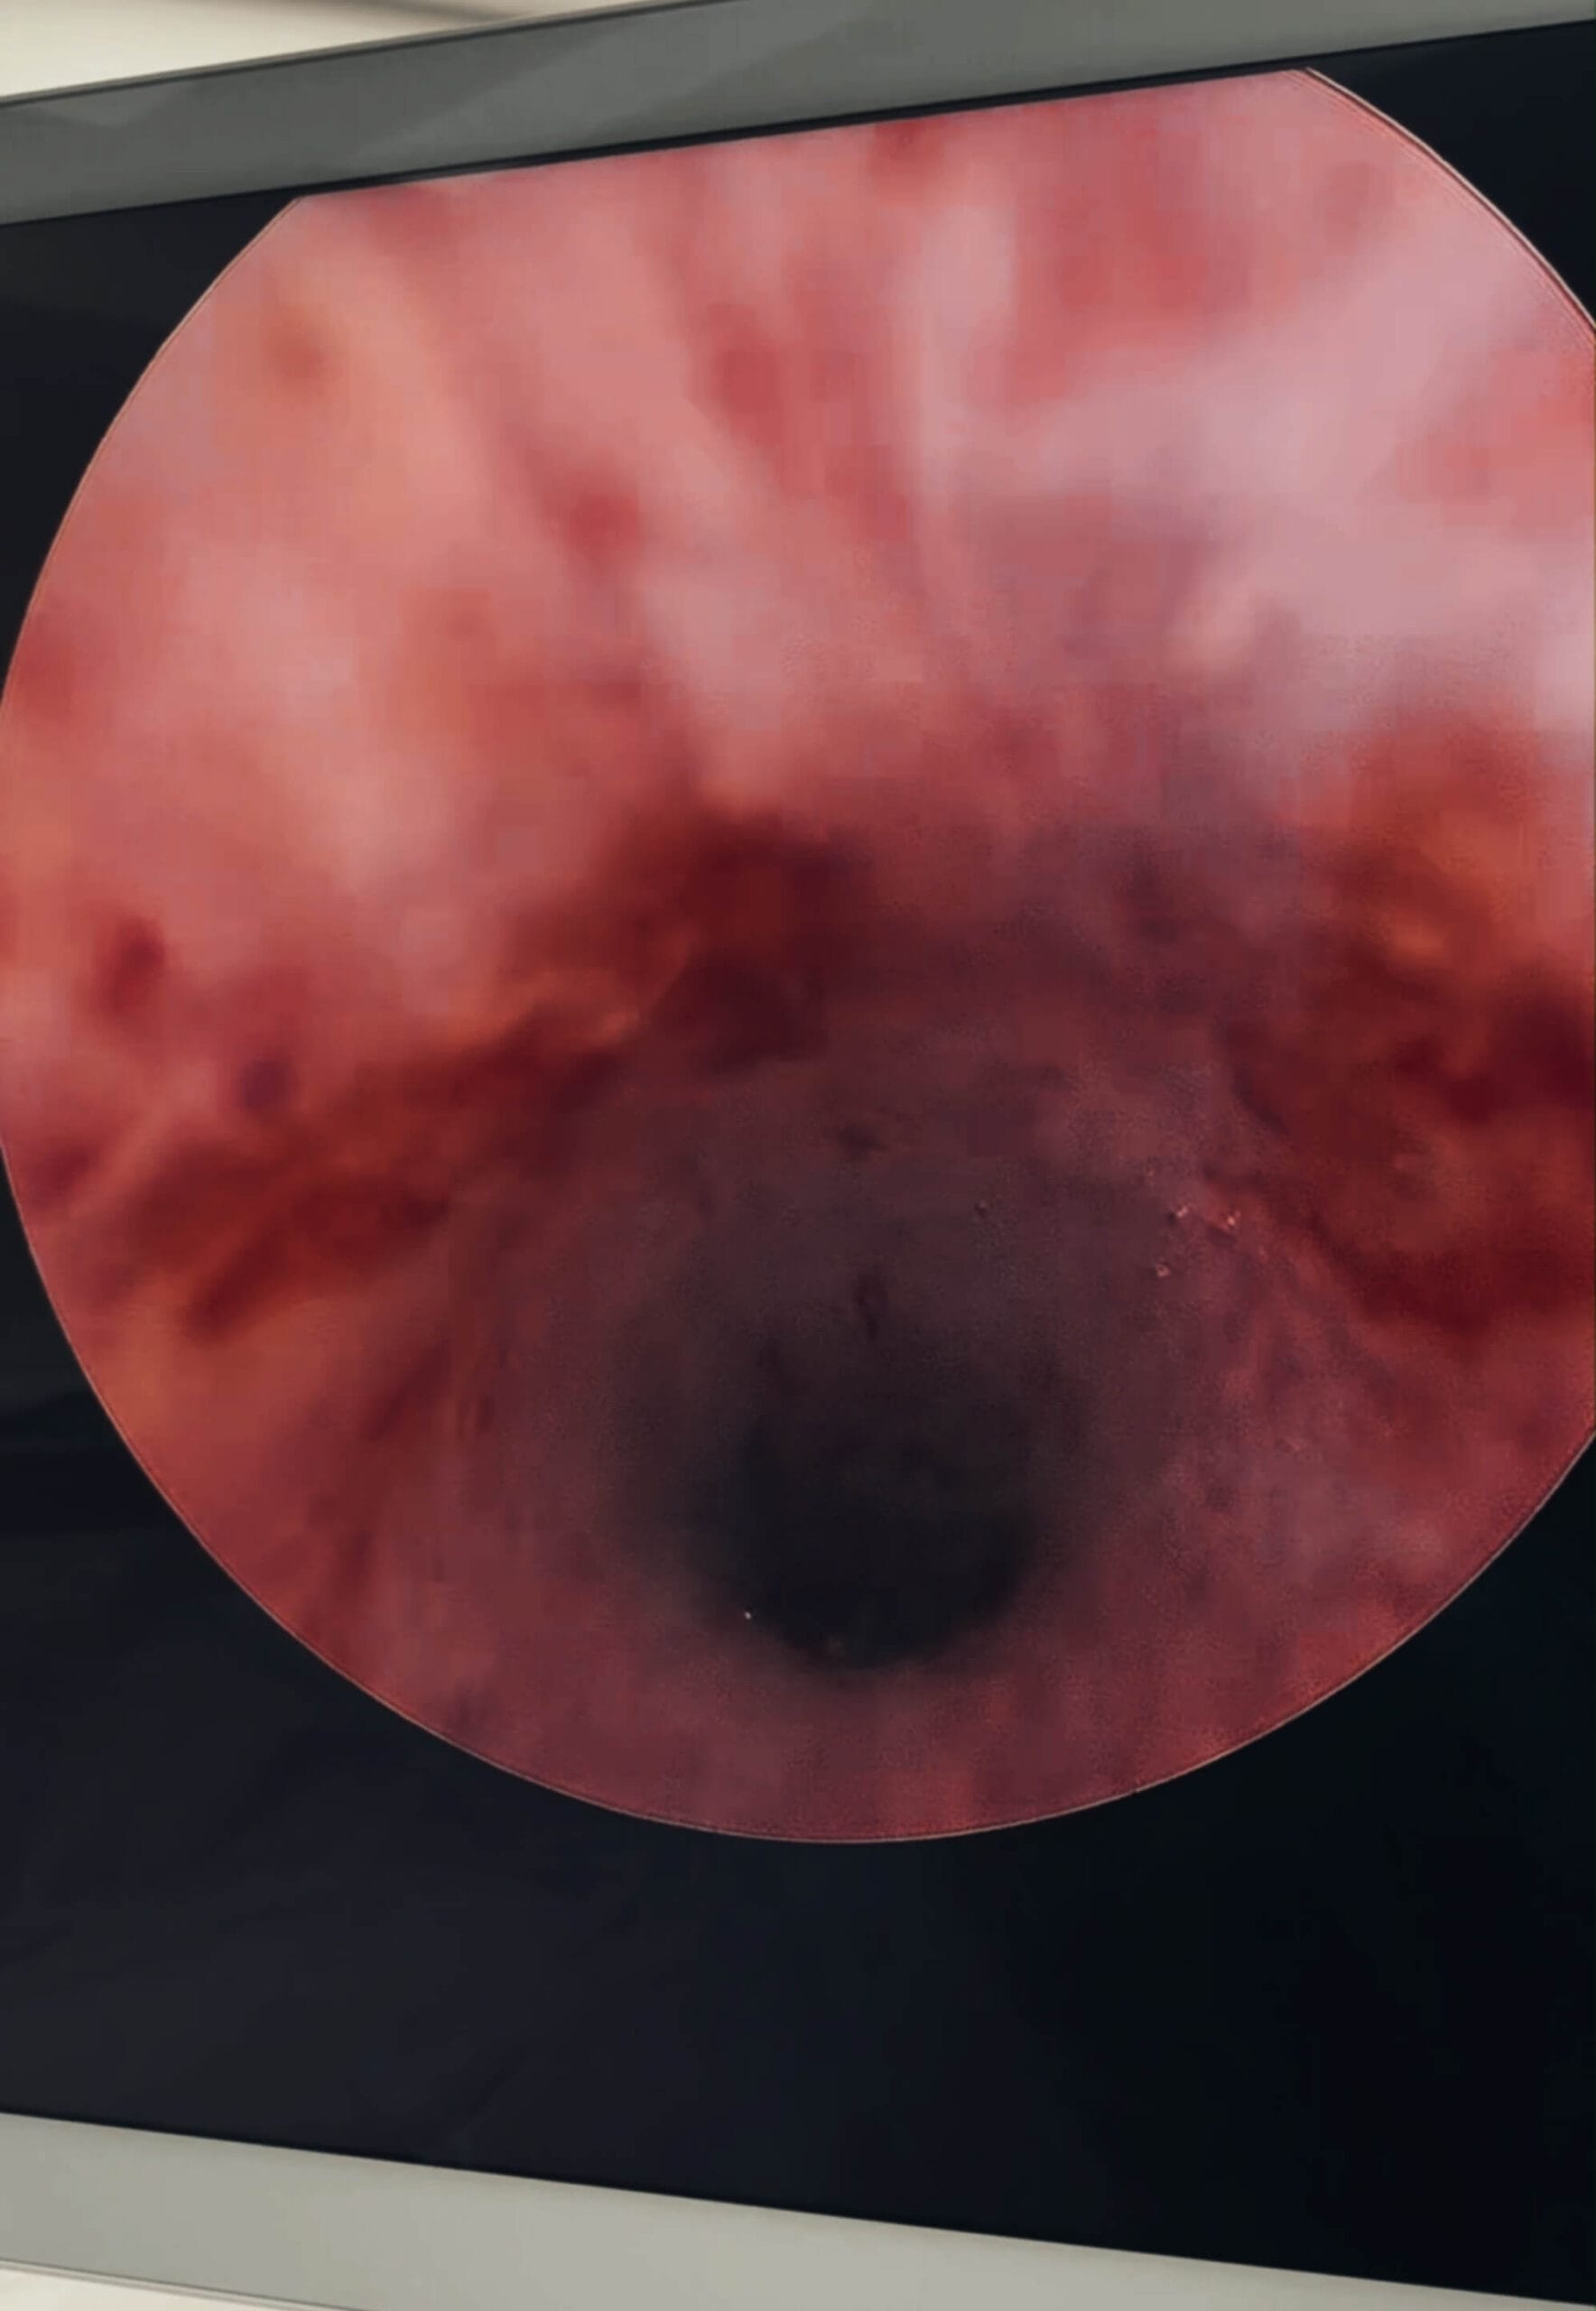

Como funciona a HOLEP

1.

Introduz-se um endoscópio pela uretra até a próstata.

2.

O laser de Holmium é usado para enuclear (destacar) o tecido prostático.

3.

O tecido removido é triturado e aspirado, deixando a uretra livre.